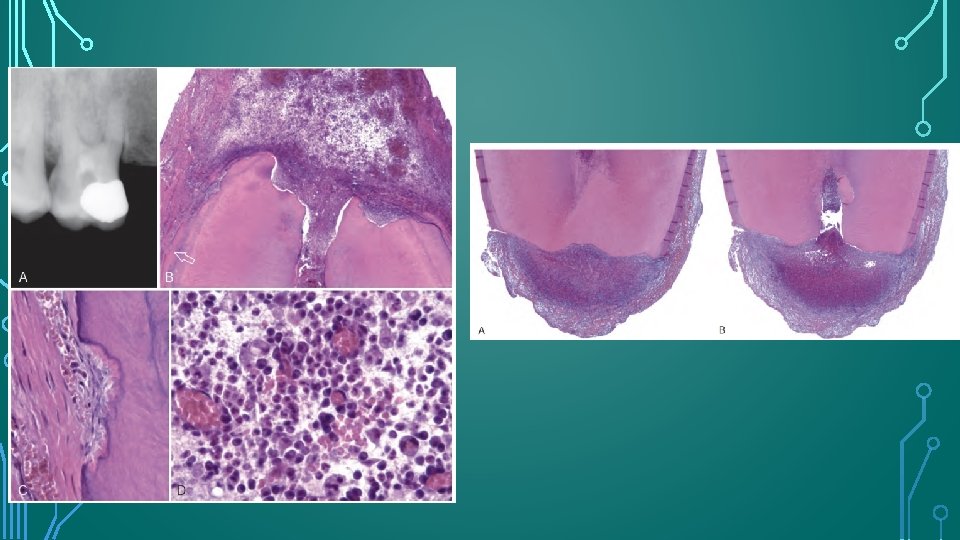

RADIOGRAPHIC FEATURES • Radiolucent , concave and sometimes ragged bowl shaped excavations • Associated radiolucency in the adjacent alveolar bone. • Complete loss of the lamina dura. • Can be seen as early as 3 - 4 weeks after traumatic dental injuries, and if it will develop , EIR always seen within 1 year after the injury. • Can have rapid onset and aggressive progression, such that complete resorption can occur within 3 months.

HISTOLOGIC APPEARANCE • Saucer or bowl shaped areas of resorption in both the cementum and dentin, with concomitant inflammation in the adjacent periodontal membrane. • Howship’s lacunae occupied by odontoclasts. • Intense inflammatory reaction in the periodontal membrane consists of a mixed-cell infiltrate that includes plasma cells, lymphocytes, and polymorphonuclear leukocytes in a granulation tissue matrix showing proliferation of capillaries. • EIR can be identified histologically 1 week after experimental replantation of teeth.